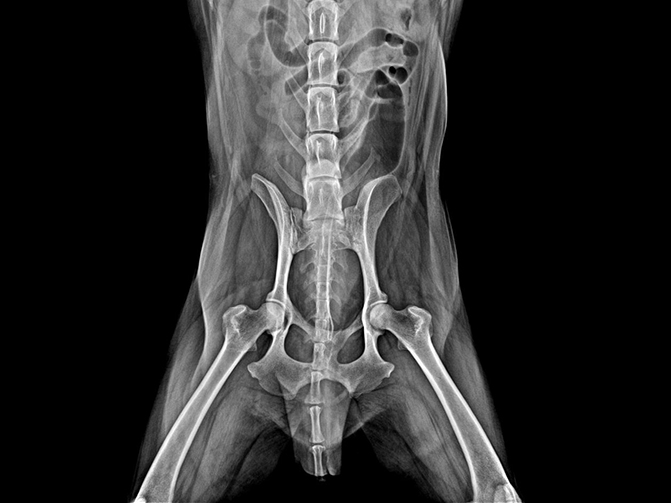

02

VET-528